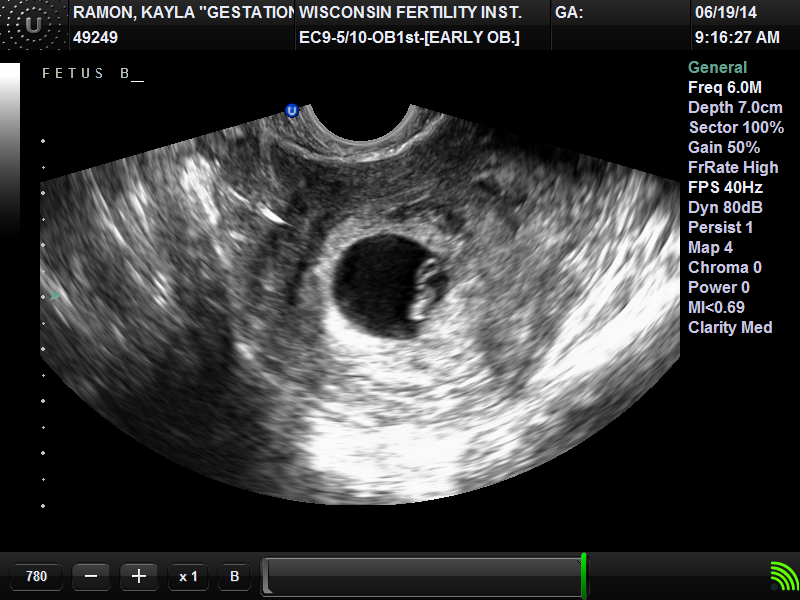

Twin B measured 6wk 1 day and heartbeat 105. 6 Week Ultrasound Twins. Twins can be detected on an ultrasound in the first trimester — as early as 4-6 weeks after you miss your period, and their heartbeats can be found at 6-8 weeks (it’s also pretty hard to distinguish two heartbeats, and having two doesn’t always indicate twins).

Ultrasounds taken at this date make sure that the pregnancy is taking place in the uterus. I am 7 1/2 weeks. Twin A measured 6wk 4 day and heartbeat 115.

A twin ultrasound at 6 weeks needs to be done vaginally to detect twins this early in your pregnancy. This is when you’ll know for sure whether or not your expecting twins. 5 weeks pregnant with twins symptoms?.